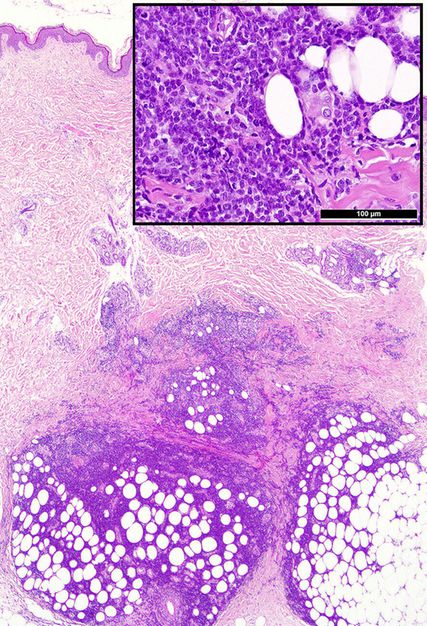

Abb. 1: Typische Präsentation einer Leukaemia cutis mit tiefenbetontem periadnexalem dermalem und interstitiellem bis kleinnodulärem subkutanem unreifzelligem (Einsatz-)Infiltrat

Die histologische Diagnose ist bei einer bekannten oder simultanen Leukämie einfach. Die meisten LC präsentieren sich als unreife klein-, blau- und rundzellige Tumoren (KBRZT) mit einer tiefer als erwarteten interstitiellen, perivaskulären, periadnexalen oder nodulären Infiltration der Dermis bzw. der Subkutis unter Aussparung der oberen Dermis (Grenzzone; Abb. 1); ALL betrifft in der Regel tiefere Strukturen.